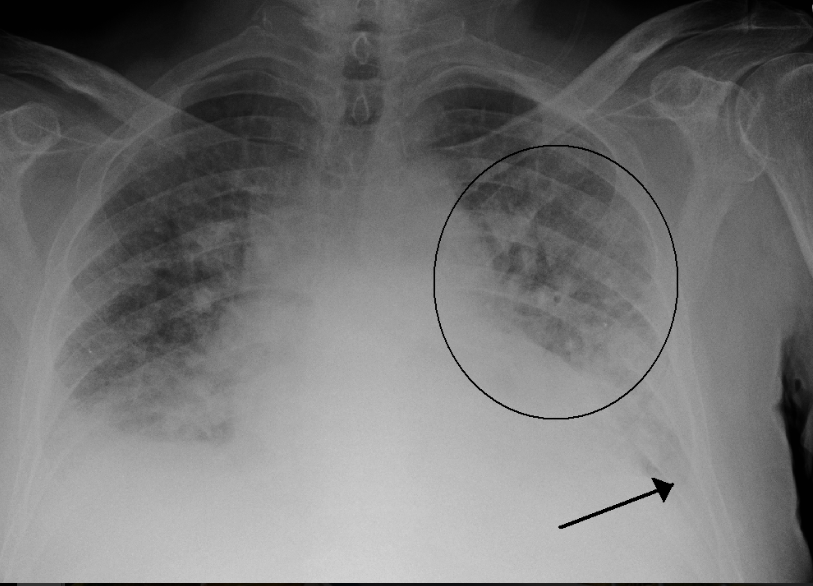

Phù phổi cấp là tình trạng mà lượng nước trong phổi tăng lên đột ngột, gây ra khó thở và suy giảm khả năng lấy và trao đổi khí. Đây là một trong những biến chứng nguy hiểm nhất trong thai kỳ, có thể gây ra hậu quả nghiêm trọng cho cả mẹ và thai nhi.

Phù phổi cấp trong thai kỳ có thể gây ra nhiều vấn đề nghiêm trọng cho mẹ và thai nhi. Nếu không được phát hiện và điều trị kịp thời, phù phổi cấp có thể gây ra những hậu quả sau:

Các dấu hiệu của phù phổi cấp trong thai kỳ bao gồm:

- Khó thở, thở gấp, thở nhanh hơn bình thường.

- Đau ngực hoặc khó chịu ở vùng ngực.

- Ho, khạc, khó nuốt.

- Sốt, cảm giác mệt mỏi, khó chịu.